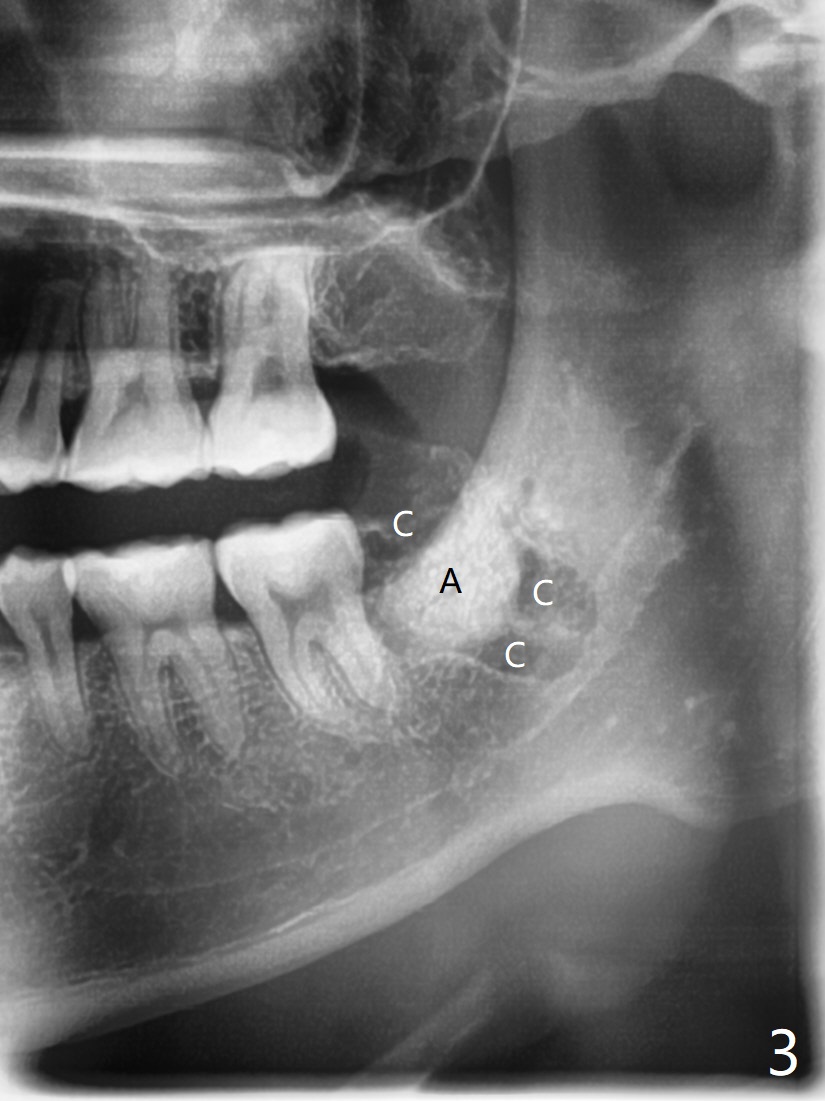

A 27-year-old man requests extraction of the tooth #17. Immediately following 4Q SRP (Fig.1), a midbuccal incision is made (Fig.2 green line) to reduce the chance of graft exposure in case of wound dehiscence because of nearly horizontal impaction of #17. The crown of the latter may be slight mesial to the distal surface of the tooth #18. In fact this is the case after flaps are raised. Since the socket is expected to be large, the graft will be placed immediately distal to the tooth #18 (Fig.2 *), while collagen plug (Fig.3,4 C) will be placed in the root portion of the socket (Fig.2 M, D (mesial and distal)) and in the gingival area (red dashed line to prevent graft material escape). Return to Plug Cement Xin Wei, DDS, PhD, MS 1st edition 06/22/2020, last revision 06/25/2020